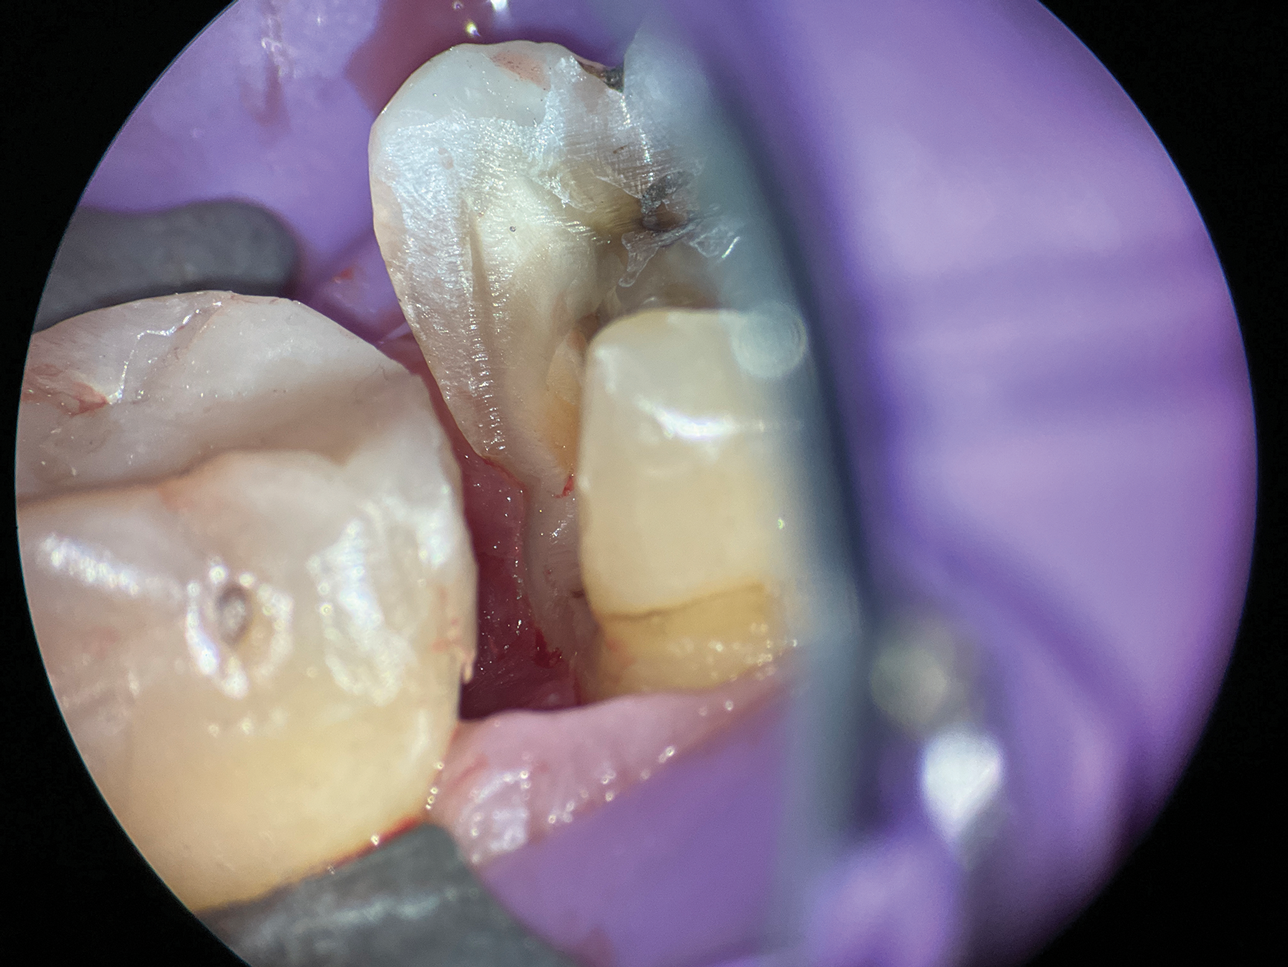

When cavity margins are located in the canine fossa due to caries, fractures, or cracks, the unique anatomy of this concavity poses a significant challenge (Figure 2 and Figure 3). Conventional matrix systems often fail to conform to its complex form and angles. This requires practitioners to possess expertise in adapting a customized matrix to suit the intricate contours of the fossa.

(2.) Close-up occlusal view of a maxillary first premolar during restorative treatment revealing a mesial structural crack.

Figure 2

(3.) Close-up occlusal view of the maxillary first premolar after removal of the thin cusps and dissection of the mesial crack, which resulted in a subgingival margin.

Figure 3